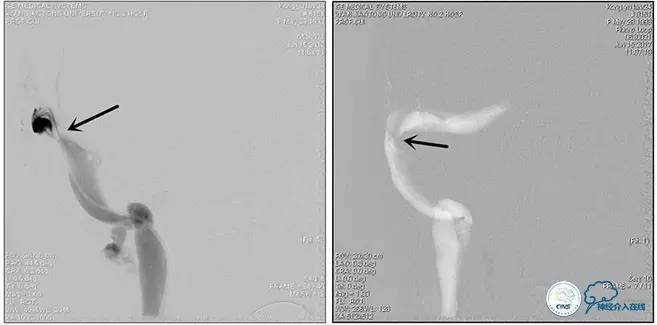

术中造影

5ml/s,总量8ml,压力100~150

手术方案

1、6mm×20mmAviator球囊(Cordis)分段对狭窄部位进行扩张。

2、植入7mm×40mmPrecise自膨支架。

术后造影

术毕远近端压力差为:0